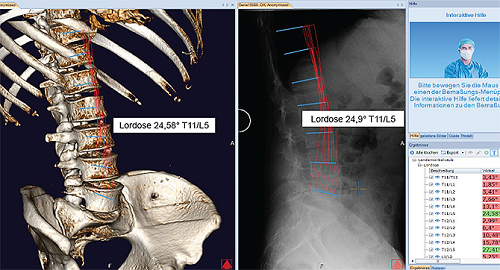

Lần đầu tiên các bác sĩ có thể tải dữ liệu hình ảnh 2D và 3D của bệnh nhân đồng thời vào một kế hoạch phẫu thuật. Cả hai hình ảnh 2D và 3D đều tương quan với nhau và được hiển thị cùng một lúc bằng cách đặt rất ít điểm tham chiếu.

Bằng cách phân tích dữ liệu hình ảnh trong tệp CT có sử dụng thuật toán phức tạp, Bác sĩ sẽ nhìn rõ sự khác biệt trong cả hai hình ảnh (ví dụ như được chụp ở tư thế đứng hoặc nằm sấp). Điều này cho phép đánh giá các cơn đau do căng thẳng hay đã thuyên giảm.

Phần mềm chấn thương chỉnh hình 3D Spine tự động đo đạc độ nghiêng của khung chậu, độ dốc của xương cùng, chỉ số cùng chậu, SVA (trục đứng dọc) và FOA (góc chéo xương đùi).

Với phần mềm MediCAD ® 3D Spine, tất cả các hành động đã thực hiện được hiển thị và cập nhật trong tất cả các hình ảnh và chế độ xem ở định dạng 2D hay 3D nhờ lập kế hoạch kết hợp trong trường hợp các phép đo, đốt sống hoặc nắn xương phức tạp.